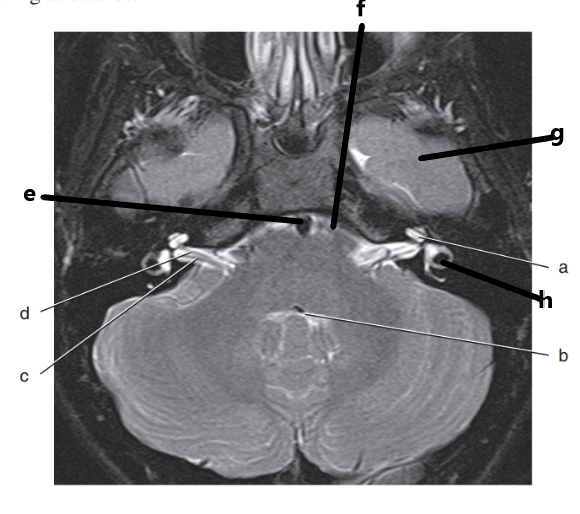

What is h ?

vestibulocochlear nerve

c and d are inside what structure ?

internal auditory canal

What is letter h ?

cerebral aqueduct